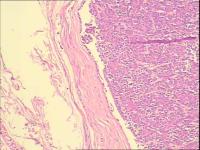

皮肤Merkel细胞癌

性别年龄37岁临床诊断

一般病史左肩部包块10年。术中见直径1厘米浅肉色包块,边界清楚。

标本名称左肩部包块

大体所见灰白带皮组织一块,直径1.5厘米,实性、包膜完整。

考虑符合:小汗腺来源肿瘤(汗腺腺瘤)

考虑汗腺瘤(多形性腺瘤可能性)。

小汗腺螺旋腺瘤

这个形态不像 merkel.,首先考虑汗腺瘤。